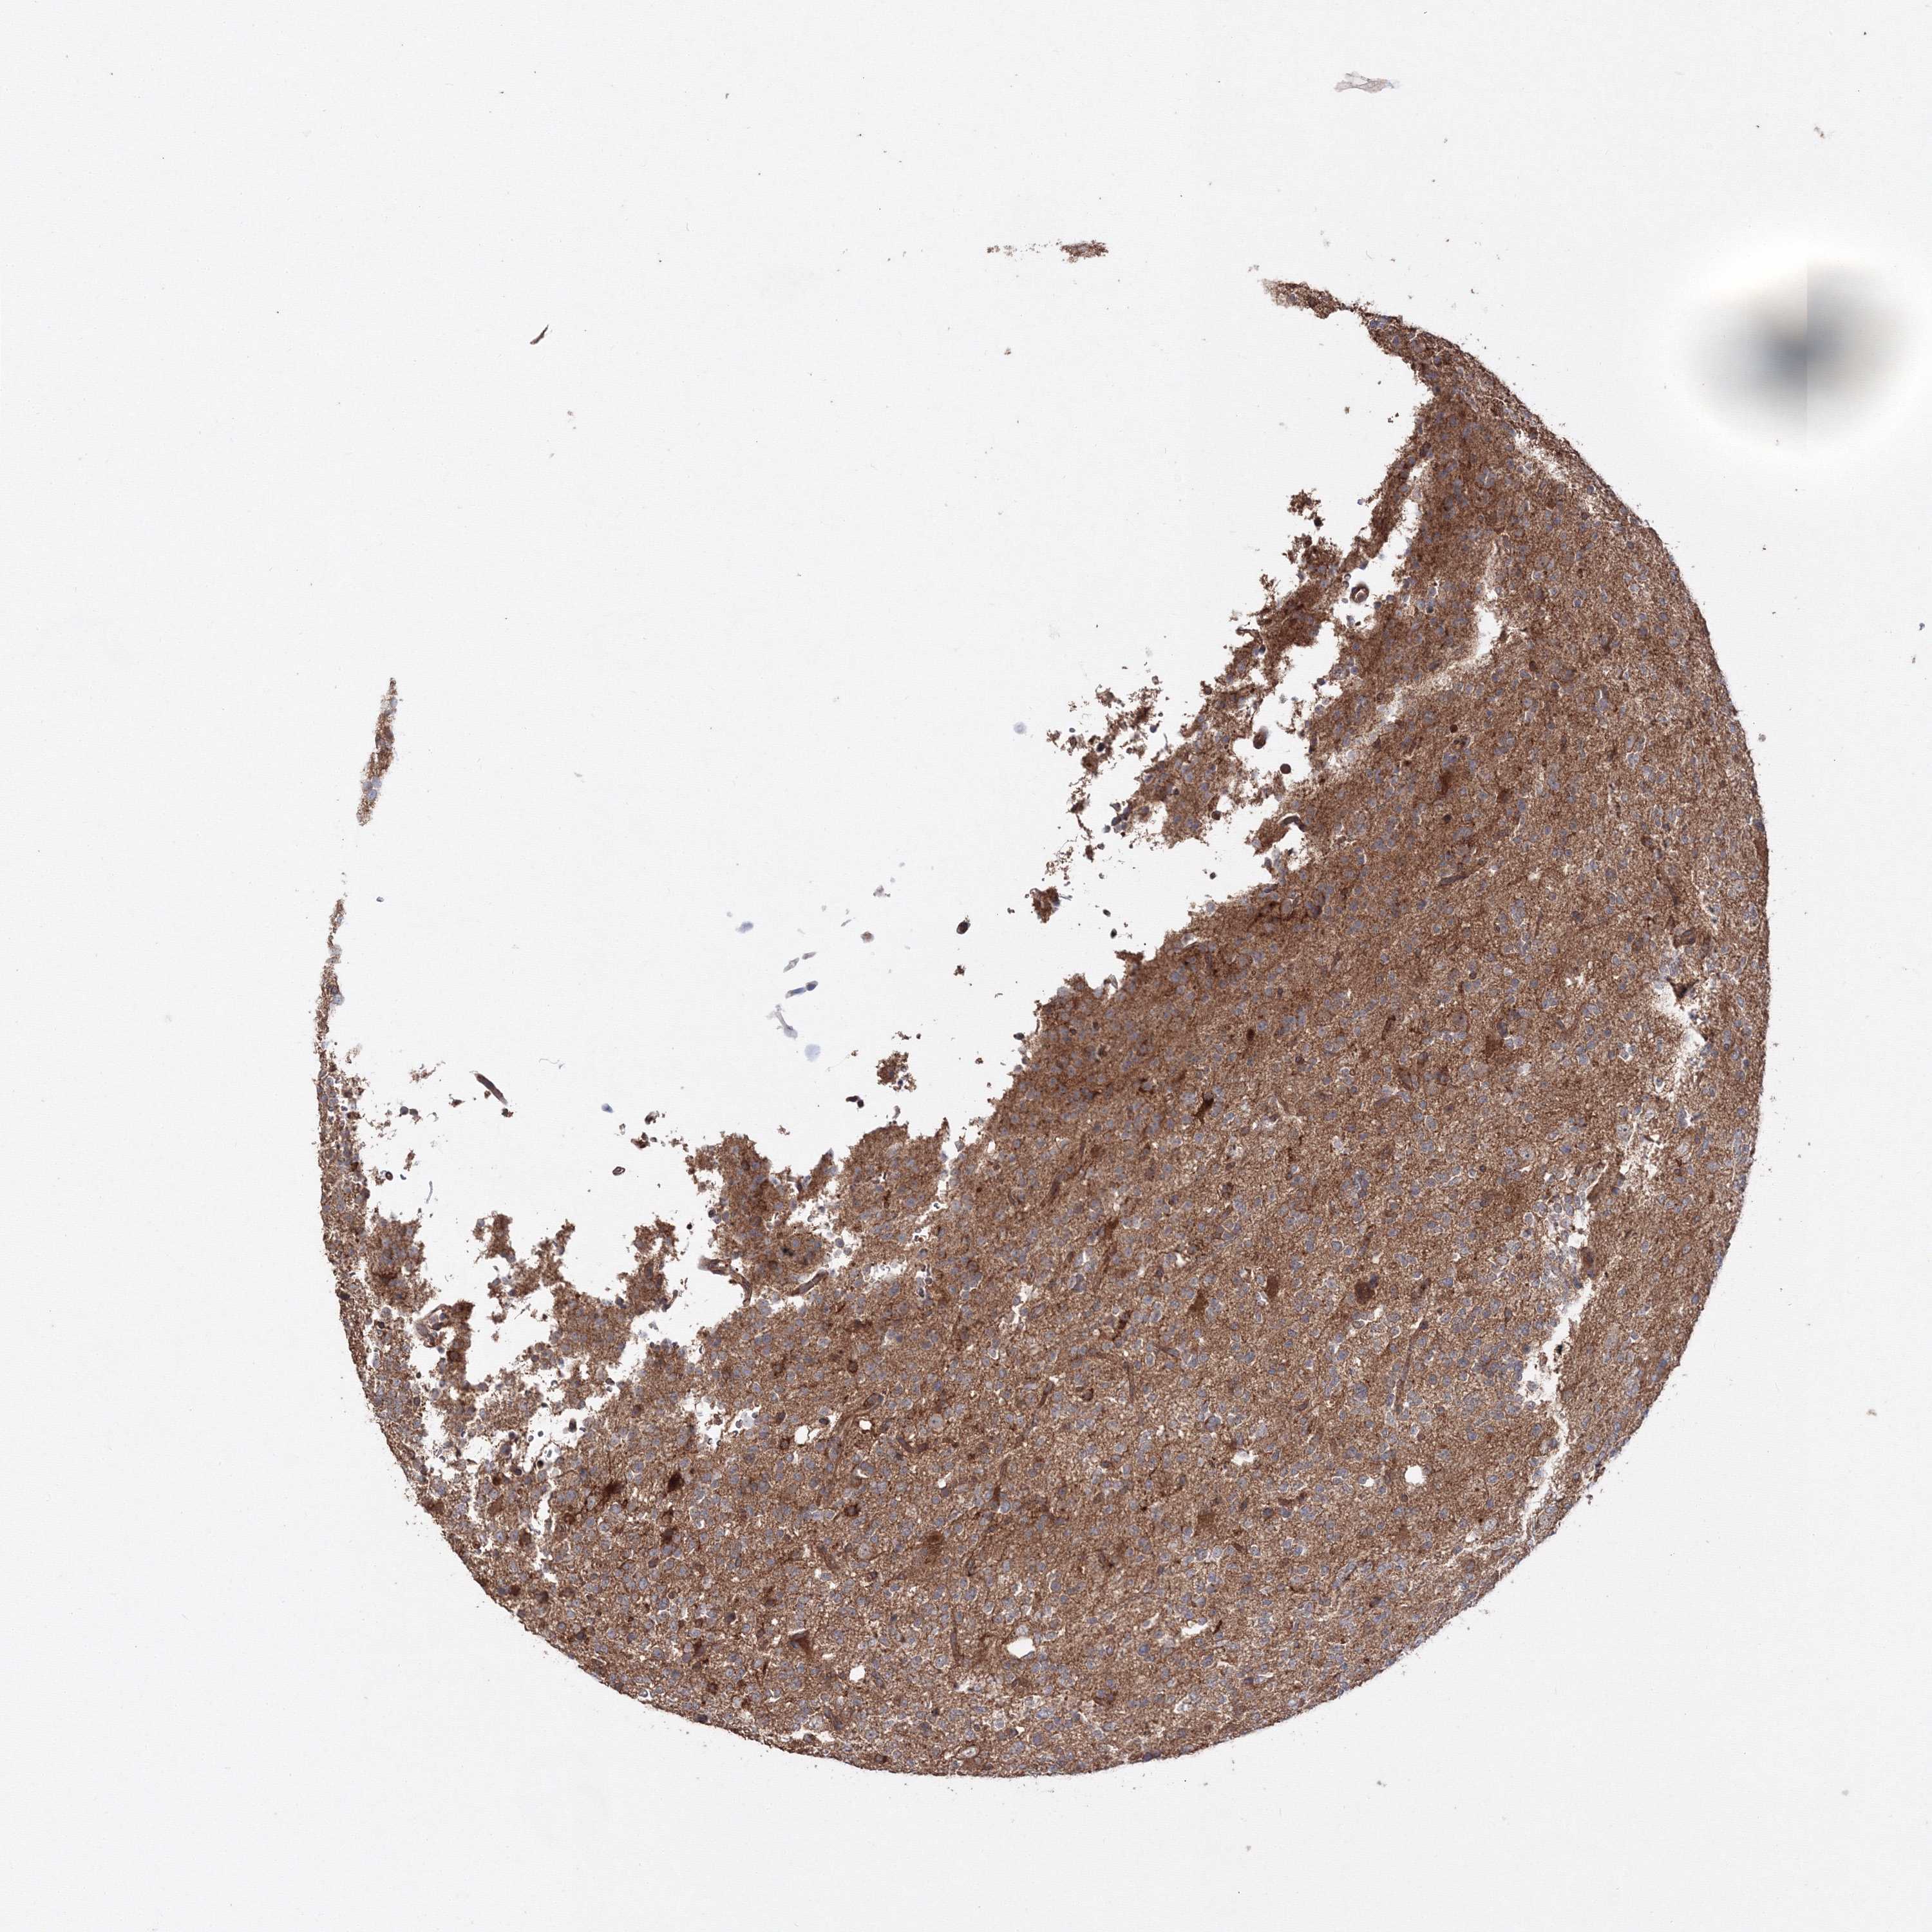

GLIOMA - Protein expressioni

A mouse-over function shows sample information and annotation data. Click on an image to view it in a full screen mode. Samples can be filtered based on level of antibody staining by selecting one or several of the following categories: high, medium, low and not detected. The assay and annotation is described here.

Note that samples used for immunohistochemistry by the Human Protein Atlas do not correspond to samples in the TCGA dataset.

Antibody stainingi

Antibody staining in the annotated cell types in the current human tissue is reported as not detected, low, medium, or high, based on conventional immunohistochemistry profiling in selected tissues. This score is based on the combination of the staining intensity and fraction of stained cells.

Each image is clickable and will lead to virtual microscopy that enables deeper exploration of all samples and also displays staining intensity scores, fraction scores and subcellular localization as well as patient and tissue information for each sample.

Antibody HPA037525

Antibody HPA037526

Staining

High

Medium

Low

Not detected

Intensity

Strong

Moderate

Weak

Negative

Quantity

>75%

75%-25%

<25%

None

Location

Nuclear

Cytoplasmic/membranous

Cytoplasmic/membranous,nuclear

Glioma, malignant, Low grade

Glioma, malignant, High grade

Glioblastoma, NOS